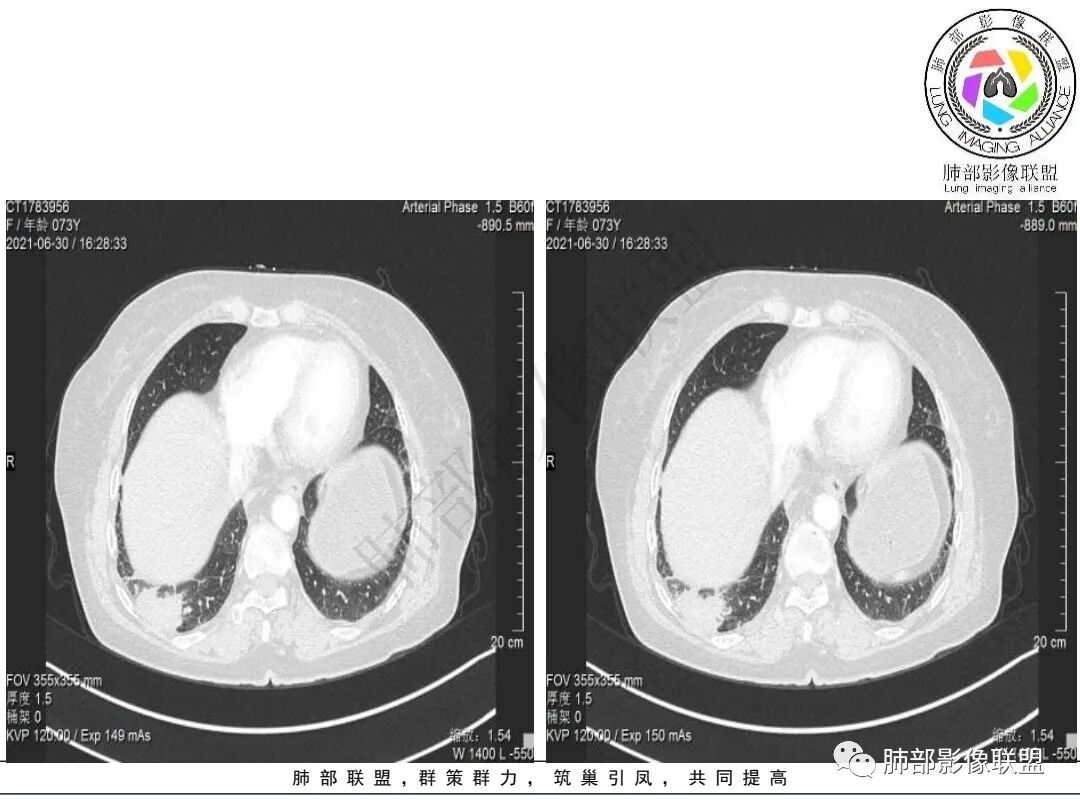

右肺下叶指套样高密度影,边界清楚,形态欠规则,累积多个叶段,平扫密度均匀,增强扫描不均匀强化,后纵隔淋巴结肿大,淋巴结内可见不均匀坏死,强化,女性,73岁,无实验室指标,考虑恶性:腺癌,鳞癌?神经内分泌癌(大细胞?),淋巴上皮瘤样癌。加一个转移瘤。

右下肺肿块,多发浅分叶呈锯齿状,有指样突起和胸膜牵拉,不均匀强化,肿块内血管增粗模糊,后纵隔淋巴结肿大坏死融合呈冰冻状,定性恶性,低分化腺癌>小细胞肺癌。

老年女性,有桶状胸,长期吸烟?右肺下叶占位并纵膈7组,肺门10组淋巴结明显肿大融合,有不均匀性强化,肺内可见下叶支气管外压性狭窄,管腔近段感觉支气管没有影响,整体病灶成支气管走形,边界清楚,考虑恶性可能性大,小?

考虑小细,纵膈及右侧肺门淋巴结肿大并左下肺小叶间隔增厚,提示周围及中央淋巴管转移,左心房及左下肺静脉受累。

2.右肺下叶不规则实性密度块影,占据外后基底段及背段较大范围,可见轻度分叶、毛刺及棘状突起,未见明显胸膜牵拉及凹陷。

3.右肺下叶支气管轻度狭窄,病灶内见部分充气支气管征,外后基底段不能连续跟踪。

轻度不均匀强化,病灶内小血管显示不满意,未见明确坏死区。

4.右肺门及纵隔见多处增大淋巴结,不均匀环形强化,后下纵隔(隆突下)肿大淋巴结十分显眼!